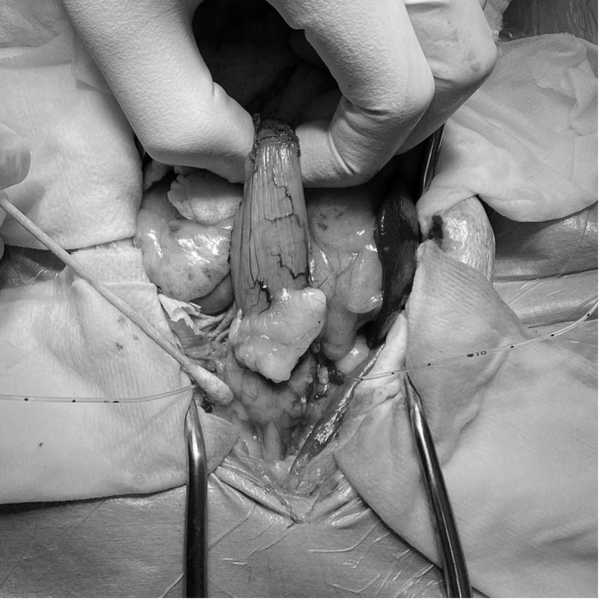

体重5.0kg(BCS3/5) 体温38.9℃ 心拍数114回/分 呼吸数30回/分 一般状態 :活動性100% 食欲100% 意識レベル 正常 一般身体検査 :特筆すべき異常所見なし 血液化学検査:異常所見なし 血液凝固系検査:TAT含め正常値 胸部X線検査:特記すべき異常所見なし 超音波検査:膀胱では膀胱頸部全周において腫瘤病変を認め、前立腺に連続する。この腫瘤は前立腺に主座し膀胱内へ伸展している形態である。(図1)前立腺の被膜構造は正常であり、腫瘤の膀胱外への浸潤は認められない。また周囲リンパ節は正常構造である。 尿道カテーテル採尿:尿沈渣では異型性を強く伴う大型の上皮系細胞が多数集塊を形成して認められる。

第24病日手術を実施した。胸骨剣状突起から恥骨前縁までの腹部正中切開を行い膀胱、前立腺へアプローチした。左右の尿管を確保し、膀胱移行部を露出後膀胱の近位で左右尿管を離断した。その後尿管にカテーテルを挿入し保持した。膀胱と前立腺、近位尿道を周囲脂肪組織から剥離し、前後膀胱動脈、前立腺動脈を処理し、最後に前立腺から十分距離を確保して尿道を骨盤腔内で結紮離断した。その後、左右尿管を腹壁に造瘻した孔を貫通させ、包皮外側の皮膚に縫合した。(図3,4)術後は左右尿管移設部位にカテーテルを留置し、入院管理を行った。入院5日目にカテーテルを抜去し、尿管移設部位からの尿排出を確認した後に退院となった。病理検査結果は、尿路上皮癌(移行上皮癌)完全切除であった。術後14日目に抜糸を行い、同日ラパチニブを開始した。またNSAIDsとしてフィロコキシブを併用した。 経過は良好であり、ラパチニブ開始から6ヵ月後に再発や転移が認められなかったことから、ラパチニブとフィロコキシブを中止し、現在術後約1年が経過するが再発や転移は認められていない。